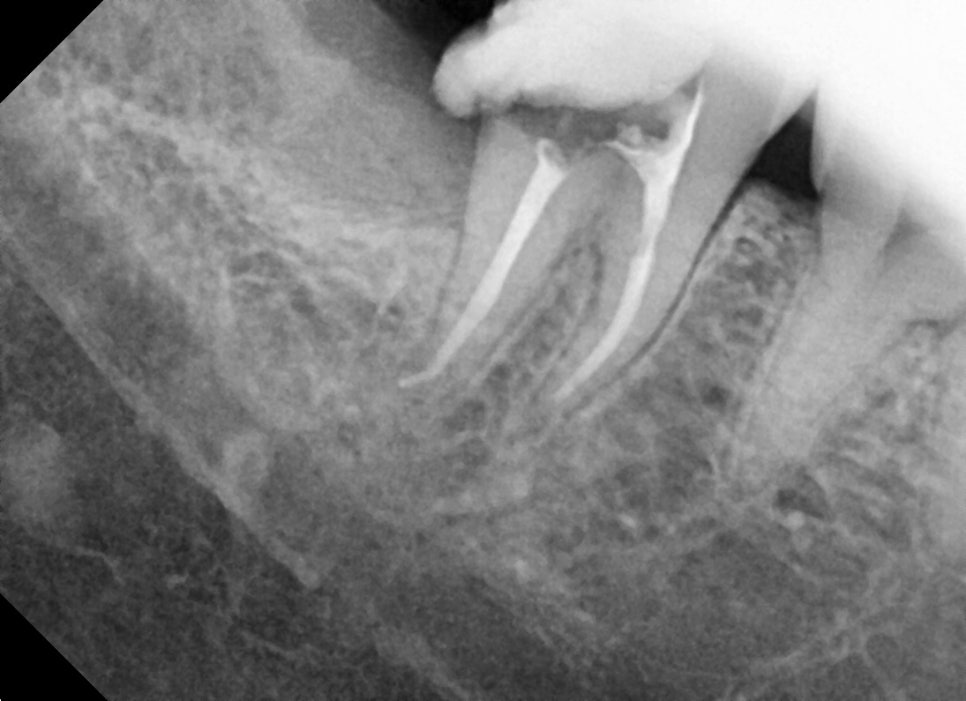

치아 뿌리가 조금 휘어있네요.

신경치료 마무리 날은 더 신경 써서 꼼꼼히 하느라 시간이 오래 걸립니다.

뿌리끝 길이를 사진으로 확인하며 마무리를 해줍니다.

사랑니 발치는 신경치료 마무리 전에 약간의 잇몸 절개와 치조골 삭제를 통해 발치를 했습니다.